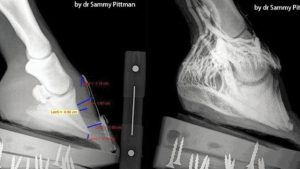

Osteotomia korekcyjna kości udowej

dr n. wet. Angelika Tobolska, dr n. wet. Korina Michalska, Aleksandra Rashid